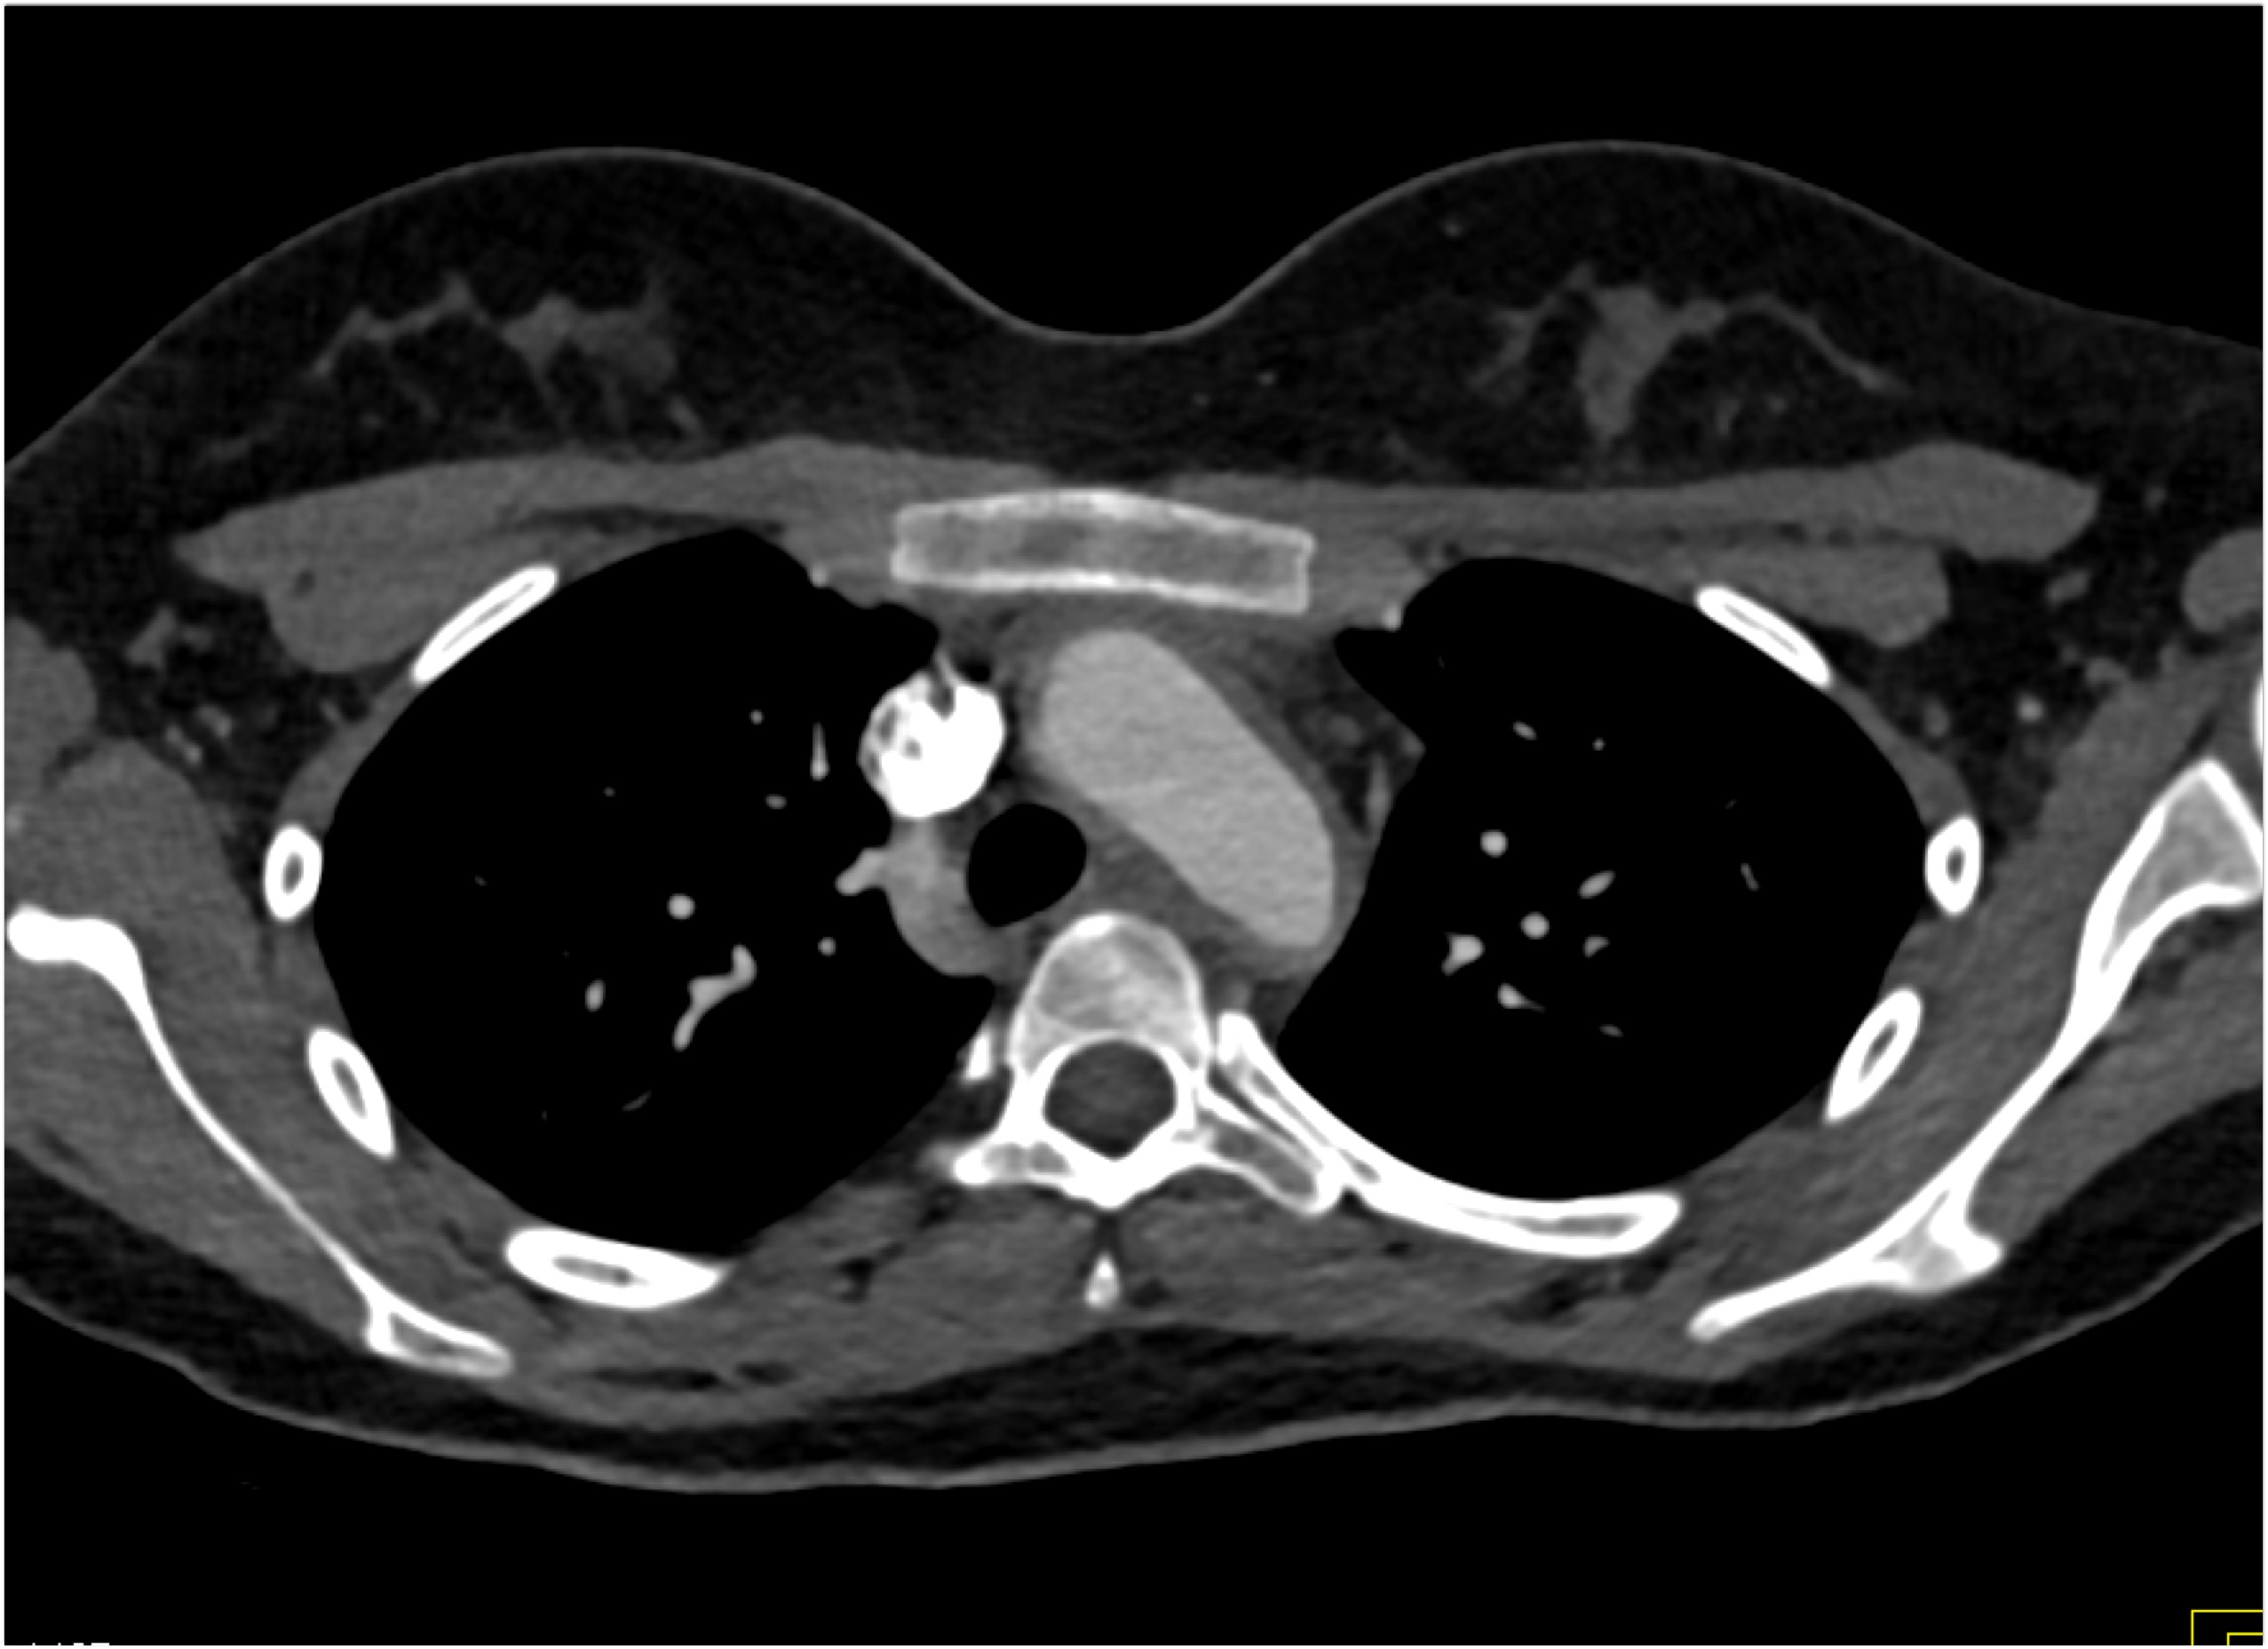

Diagnostic Case Quiz ❯ Anatomical Region Quiz: Chest

The most likely diagnosis in this case is?

Ehlers Danlos disease

Kawasaki disease

Takayasu’s aortitis

Ig4 vasculitis